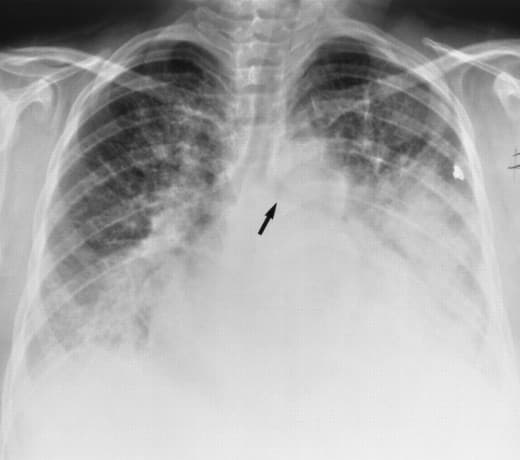

Phù phổi và những điều cần biết

Phù phổi là gì?

Phù phổi cấp là một tình trạng ngạt thở do nhiều nguyên nhân khác nhau, chỉ có thể cứu được nếu can thiệp sớm và đúng hướng. Các nguyên nhân này làm cho nước ra ngoài mao mạch phổi quá nhiều gây ra tình trạng phù phổi. Lưu lượng nước trong phổi tăng đột ngột gây nên phù phổi cấp huyết động trong 10 – 15 phút, tuy nhiên có thể tăng dần mỗi ngày một nặng trong phù phổi cấp tổn thương.

Phù phổi cấp được chia làm 3 giai đoạn đó là: giai đoạn mao mạch, giai đoạn kẽ và giai đoạn phế nang. Trên lâm sàng phù phổi cấp tương ứng với giai đoạn phế nang.